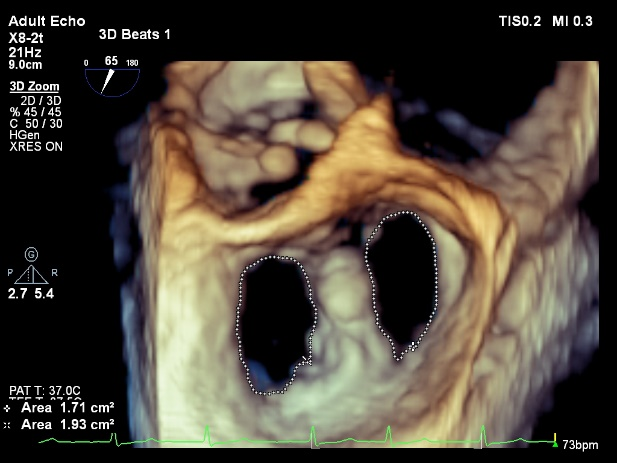

二尖瓣的经导管缘对缘修复(TEER)借鉴外科采用二尖瓣夹合装置,经股静脉(或心尖)途径,在经食道超声心动图(TEE)及X线造影机引导下夹住二尖瓣反流区的前、后瓣叶并使之接合,使收缩期二尖瓣瓣叶的间隙减少或消失,而舒张期瓣口由大的单孔变成小的双孔或多孔,从而减少二尖瓣关闭不全。这项技术因创伤小、恢复快的特点,是目前应用最广泛、证据最多的经导管二尖瓣修复术,成为了治疗MR的一种新选择,在全世界其中MitraClip应用超过17万例,目前有1000家中心开展TEER技术,国内2020年MitraClip正式上市,累计开展600余例。

术前单孔

术后双孔

超声心动图在术中作用较大,该手术对TEE的图像要求高,必须配备成像清晰、有实时三维成像功能的TEE探头及机器。此外,要求能够将超声心动图图像传送到显示屏上,以便术者实时观看、指导操作。在术中的房间隔穿刺、瓣膜的抓取及释放、术后效果的评估完全依赖超声心动图。MR的高患病率,低外科手术治疗率使得经导管二尖瓣介入治疗成为继主动脉瓣之后的又一热点赛道。TEER是目前该领域的主流技术,在全球手术量激增,并且产品迭代迅速,临床和解剖适应征不断拓展,相信在未来一段时间内将继续领跑。